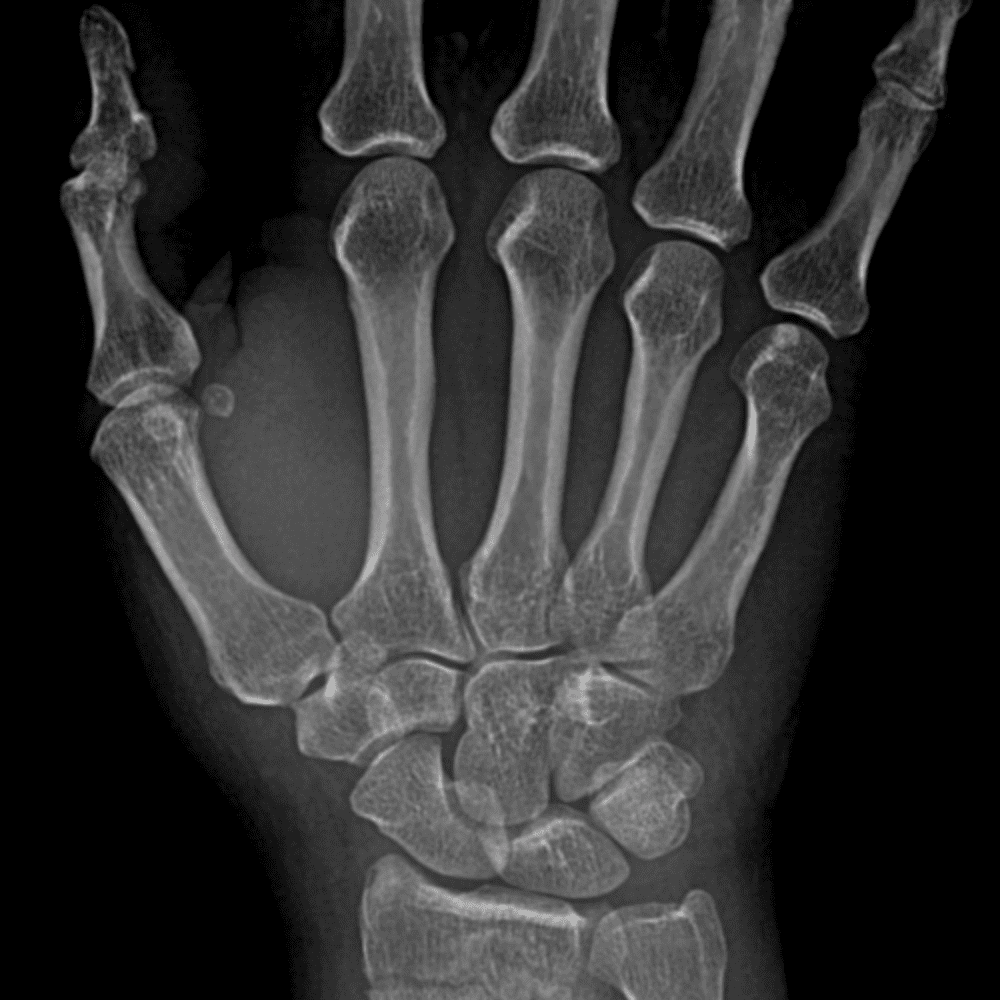

Simuliert den Dienst durch subtile oder schwierige Fälle und einige Normalbefunde.

30 Fälle